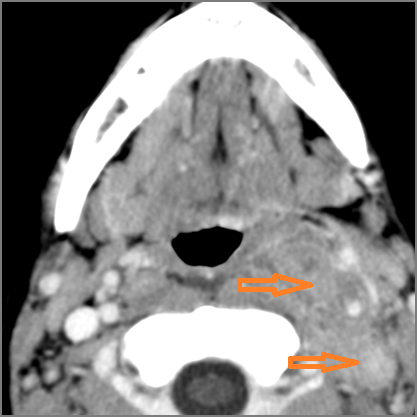

Hypopharynx, Larynx, Deep Neck and Entire Retropharyngeal Space

There is edema/abscess arising from the hypopharynx, larynx, thyroid gland or trachea.

There is edema/abscess within the adjacent deep neck, and/or retropharyngeal space.